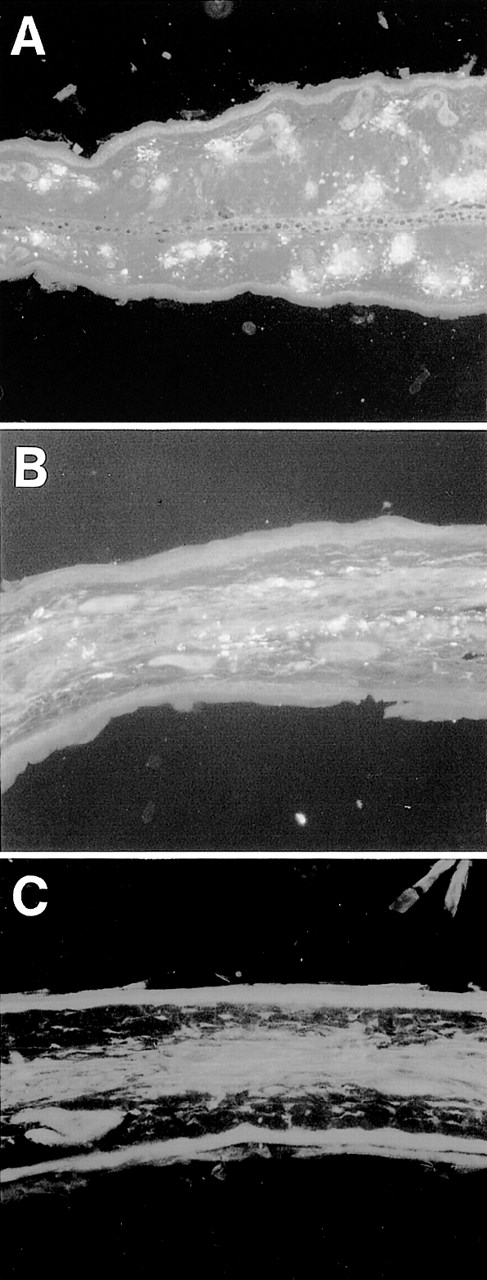

Representative histological appearance of 6-19–induced skin lesions. The sections of the ear from untreated normal mice (A) and 6-19–treated FcRγ+/− (B), FcRγ−/− (C), and TNFβ−/− (D) mice were prepared 12 days after IP injection of 6-19 hybridoma cells. Tissues sections were stained with HE (original magnification × 100). FcRγ+/− mice developed leukocytoclastic vasculitis characterized by the infiltration of PMNs and the extravasation of erythrocytes (B). FcRγ−/− and TNF−/− mice did not develop leukocytoclastic vascular lesions (C and D). Note that in (D), darkly stained cells were melanocytes due to 129 background and that small numbers of PMNs had infiltrated the skin of TNF−/− mice.

To determine whether FcγR is involved in the induction of skin vasculitis and glomerulonephritis in vivo, we injected 6-19 hybridoma cells into FcRγ+/− and FcRγ−/− mice and analyzed the development of inflammatory responses. A protocol of injecting purified 6-19 MoAb cannot be used because of its cryoprecipitability. Seven to 12 days after the IP injection of 6-19 hybridoma, FcRγ+/− mice developed vascular purpura on the skin of ears, tails, and footpads. In contrast, none of the FcRγ−/− mice injected with 6-19 hybridoma developed the characteristic purpura (Table 1 and Fig 1A). Histological examination confirmed these results (Fig 2). 6-19–treated FcRγ+/− mice exhibited leukocytoclastic vasculitis in the skin, characterized by infiltration of polymorphonuclear leukocytes (PMNs) and extravasation of erythrocytes (Fig 2B). In contrast, treated FcRγ−/− mice did not show any indication of inflammatory responses (Fig 2C), remaining the same as untreated normal mice (Fig2A). Serum levels of IgG3 (Table 1) and the presence of intracapillary PAS-positive materials, likely ICs with cryoglobulins, in the skin were comparable in FcRγ+/− and FcRγ−/− mice. Indeed, immunofluorescence staining of sections of affected skin by anti-IgG3 MoAb demonstrated that IgG3 deposits corresponding to the PAS-positive material in the vascular lumens were present in both groups of mice (Fig 3A and B, see page 3858). These results indicate that skin vasculitis is completely inhibited in FcRγ−/− mice despite the fact that the depositions of ICs containing IgG3 were similar to those in wild-type mice.